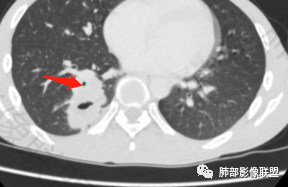

右肺下叶背段实变影,宽基底与胸膜相连,边缘毛糙,内部可见空洞影,空洞壁光滑,内部可见坏死,近端支气管显示不清,远端胸膜下间隙可见,青年男性,考虑结核,鉴别NTM,鳞癌

青年男性,呼吸道症状起病,右肺下叶背段肉芽肿样变,边缘分叶,胸膜糊墙,略牵拉,内部密度不均,空洞无物,壁整,支气管通畅,卫星灶,玫瑰结状小叶中心性结节及少量树芽;中度强化,湖泊样坏死,内部无完整血管影:结核可能性、鉴别:坏死性支原体肺炎、鳞癌。

有晕征,第一感觉像是感染类病变,仔细看下叶支气管不通畅,感觉有阻塞,先考虑感染类病变,肺链?隐球?毛霉曲霉?TB?NTM?鉴别诊断肉瘤类,肉瘤样癌,类癌。

青年,咳嗦,指标基本正常,右肺下叶不规则软组织密度影,密度不均,有坏死,小空洞,宽基底与胸膜相连,支气管觉得通畅,考虑感染,鉴别结核

35岁男性患者,病史及实验室检查无免疫受损相关依据,无感染毒血症状,炎症指标CRP、降钙素原、血沉均正常,曲霉抗原阴性;CT提示右下背段肿块影,边缘膨隆,有分叶及短毛刺,偏心空洞,增强扫描提示不均匀强化,有坏死,考虑:1.腺癌 2.隐球

中年男性,咳嗽2月余,pct正常,首先排除普通肺炎。右下背段肿块,边缘毛糙,浅分叶,与胸膜宽基底相连,有坏死(无液平,为凝固性坏死,不考虑脓肿),常规考虑结核隐球菌,鉴别恶性肿瘤

青年男性患者,间断咳嗽、少量黄白痰2月,胸部CT:右肺下叶后基底段类圆形病灶,边界清楚,周围磨玻璃,内部有空洞形成,空洞干净,考虑炎性病变,脓肿,隐球,结核,鉴别鳞癌

右肺下叶肿块,分叶,近端支气管部分堵塞,部分沿壁厚,沼泽样强化,可见空洞,邻近胸膜少量积液,膈肌牵拉,考虑肿瘤,鳞癌?鉴别NTM

青年男性,慢性病程,右肺下叶团块影,形态不规则,内见空洞,壁厚薄不均,不均匀轻度强化。考虑恶性,肺癌,肿标中角蛋白19增高,倾向于鳞癌,鉴别结核。

中年男性,有咳嗽咳痰病史俩月,亚急性病程,炎性指标不高,右肺下叶后基底段近胸膜下不规则肿块,边缘膨隆毛糙,支气管近端阻塞,内有厚壁空洞,无液平,洞壁不均匀强化,周围支气管壁厚,远端有点片影,考虑鳞癌可能性大,鉴别肺脓肿和肺结核。但是血沉不快,crp不高,有点不大符合炎性。